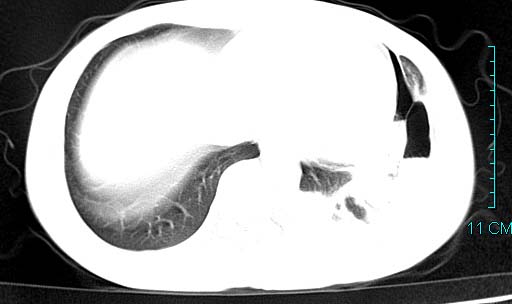

以下是引用qian在2006-3-28 14:32:00的发言:[br]左肺下叶大片状阴影,密度不均,见有条片影和空洞及气液平,少量胸腔积液伴有胸膜增厚,从图像看积液密度比水的密度高,结合病史,考虑左下肺化脓性炎症伴有脓胸。

以下是引用wawaquan在2006-3-28 22:25:00的发言:[br]左上肺舌段多发斑片影。结合“男24y咳嗽咳痰气促伴高热(38.5--39.5)20多天”及穿刺史,[br]考虑1 左下肺化脓性炎症;2脓胸。

以下是引用乡医在2006-3-28 18:37:00的发言:[br]左侧多发液气平面结合患者男24y咳嗽咳痰气促伴高热(38.5--39.5)20多天,查胸水:ldh239.3,总蛋白59.19,tb-ab阴性,利凡它试验+,红c2.7*109,白c1.08*109,分类淋巴92%分叶8%,考虑1脓胸2肺隔离征感染